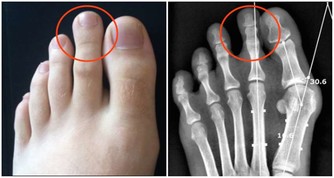

三、在抬腳時可引濁氣下行排出,升清降濁正氣倍增,體內正常細胞大曾活躍,癌細胞自然死亡。